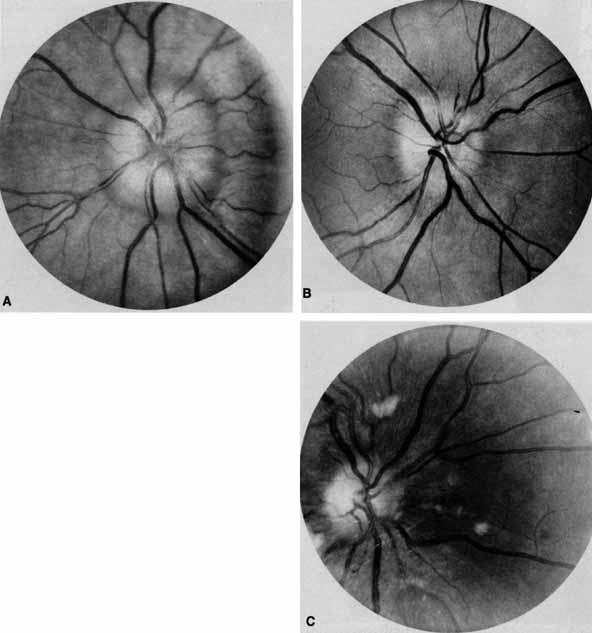

Ophthalmoscopy can be very helpful in orbital diagnosis. Optic disc edema may be caused either by papilledema (increased intracranial pressure) (Fig. 11A), papillitis (anterior optic neuritis) (Fig. 11B), or vasculitis (e.g., lupus erythematosus, sarcoidosis, Wegener's granulomatosis, and giant cell arteritis) (Fig. 11C).12 Papilledema (Fig. 11A) is usually present with near-normal visual function, although some patients may lose vision.9 In contrast, papillitis (Fig. 11B) characteristically leads to reduced visual function, commonly is associated with orbital pain, and is associated with inflammatory cells in the vitreous overlying the disc. Optic disc vasculitis (Fig. 11C) may be present with other findings of vasculitis, and commonly is associated with poor acuity and evidence of vascular occlusion (e.g., cotton-wool spots, hemorrhages). The differential diagnosis of the swollen, erythematous disc is discussed elsewhere in these volumes.

Fig. 11 A. Papilledema caused by pseudotumor cerebri. Visual acuity is 20/15 and the visual field is normal. B. Papillitis of anterior optic neuritis. Visual acuity is 20/400 with a relative afferent pupillary defect and a central scotoma. C. Vasculitis of optic disc caused by lupus erythematosus. Visual acuity is 20/200, there is a relative afferent pupillary defect, and a cecocentral scotoma. Note cotton-wool spots.

Optociliary shunts (Fig. 12A) develop as a result of long-term obstruction of the central retinal vein. This may occur secondary to optic nerve meningiomas,13 optic nerve gliomas,14,15 optic nerve meningoceles,16 central retinal vein occlusions,17 optic nerve sarcoidosis,18 craniosynostosis,19 optic nerve arachnoid cysts,20 optic disc drusen,21 and papilledema.15 Congenital optociliary shunts, which are exceedingly rare, have not been associated with optic neuropathy or orbital disease.22,23 The presence of optic nerve pallor, poor acuity and optociliary shunts generally implies an optic nerve meningioma in the absence of other funduscopic findings (Fig. 12B).13

Fig. 12 A. Optociliary shunt vessels (arrow) are present on the surface of an atrophic optic disc. The patient's visual acuity was hand motions. The patient demonstrates 2 mm of proptosis. B. Gadolinium-enhanced, fat-suppressed magnetic resonance imaging (MRI) demonstrates an intraorbital optic nerve sheath meningioma (arrow).